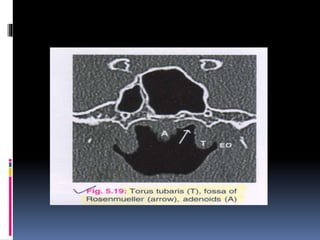

 Coronal sections of the nasopharynx show the-

eustachian tube opening, torus tubaris. Fossa of

rosenmuller and the adenoids, if present.

 Asymmetry of the Fossa of rosenmuller should

be looked for.